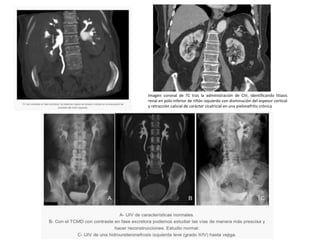

Imagen coronal de TC tras la administración de CIV, identificando litiasis

renal en polo inferior de riñón izquierdo con disminución del espesor cortical

y retracción calicial de carácter cicatricial en una pielonefritis crónica

Imagen coronal deTC tras la administración de CIV, identificando litiasis renal en polo inferior de riñón izquierdo con disminución del espesor cortical y retracción calicial de carácter cicatricial en una pielonefritis crónica